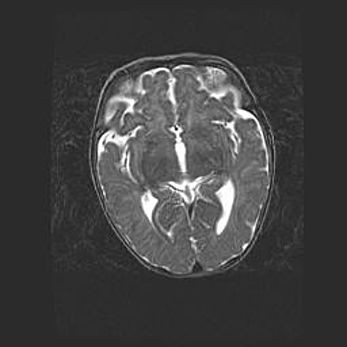

Лейкомаляция с кистозно-глиозной дегенерацией головного мозга.

Возраст: 2 месяца 25 дней

Вес: 6400 г

Окружность головы: 40 см

Срок гестации: 41 неделя

Лейкомаляцию относят к ишемически-гипоксическим повреждениям головного мозга, диагностируемым у новорожденных. При лейкомаляции в головном мозге обнаруживают очаги некроза, возникшие после тяжелой гипоксии и нарушения кровотока. В процессе морфогенеза очаги проходят три стадии: 1) развития некроза, 2) резорбции и 3) формирования глиозного рубца или кисты. Перивентрикулярная лейкомаляция (ПЛ) встречается примерно в 12% случаев среди новорожденных, обычно – у недоношенных детей, причем, частота ее зависит от массы, с которой младенец появился на свет. Наибольшее число малышей страдает лейкомаляцией, если масса при рождении 1500-2500 г.